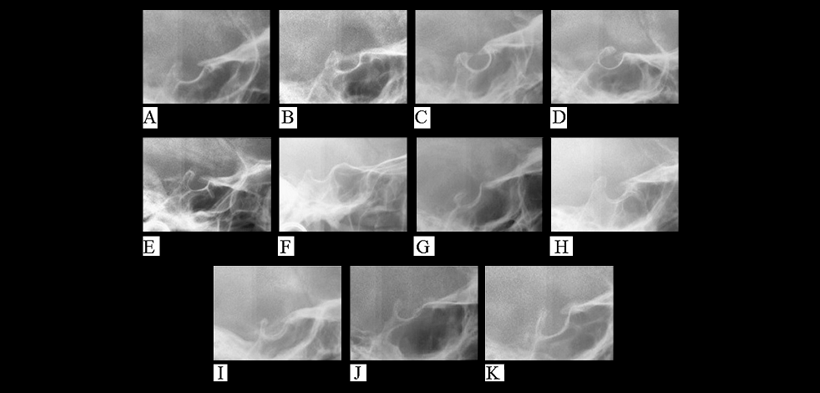

La calcificación parcial del ligamento interclinoideo se define como un puente incompleto. En la figura 1 se muestra las principales alteraciones morfológicas de la silla turca, es importante hacer una práctica constante para identificar cada una de ellas y no pasarlas por alto.

Fig. 1. Anomalías de la silla turca. (A) Silla turca Normal. (B) Silla turca en puente tipo A (en cinta). (C) Silla turca en puente tipo B (extensión de los procesos clinoides. (D) puente incompleto. (E) Hipertrofia de los procesos clinoides posteriores. (F) Hipotrofia de los procesos clinoides posteriores. (G) Irregularidades (muescas) en la parte posterior de la silla turca. (H) forma piramidal del dorso de la silla turca. (I) Doble contorno de la piso de la silla turca. (J) Pared anterior oblicua. (K) Contorno oblicua del piso de la silla turca.